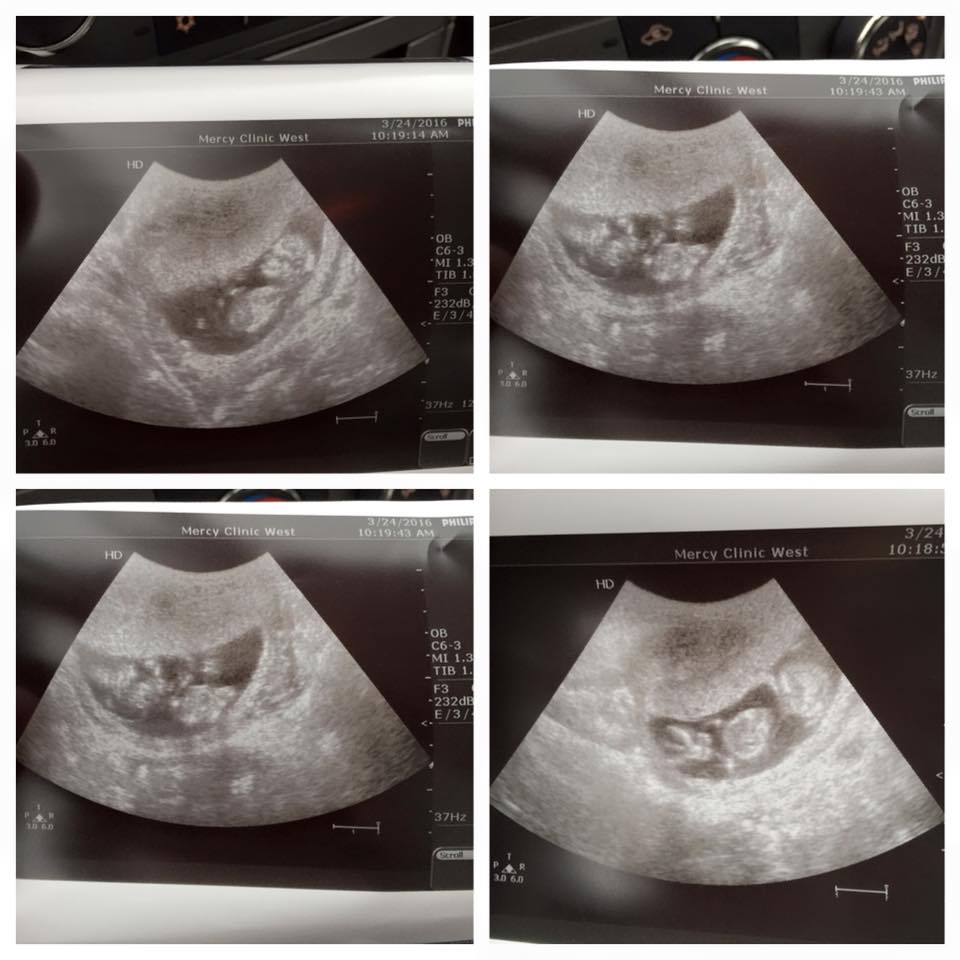

The top is baby A, bottom is baby B. 13 weeks today and i was just curious to see what everyone thought?

The second and third picture are the same. Very unclear shots.

There are no nubs or anything to guess on.

I don't see a nub in any of them.. Congrats on your twins!!!